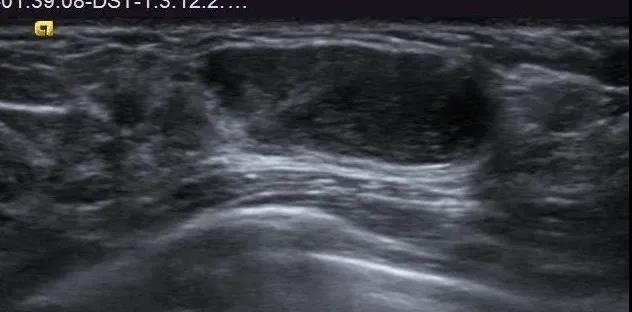

良性叶状肿瘤:肿块较小,边界清,无明显包膜,低回声,未见明显血流,比较难诊断。